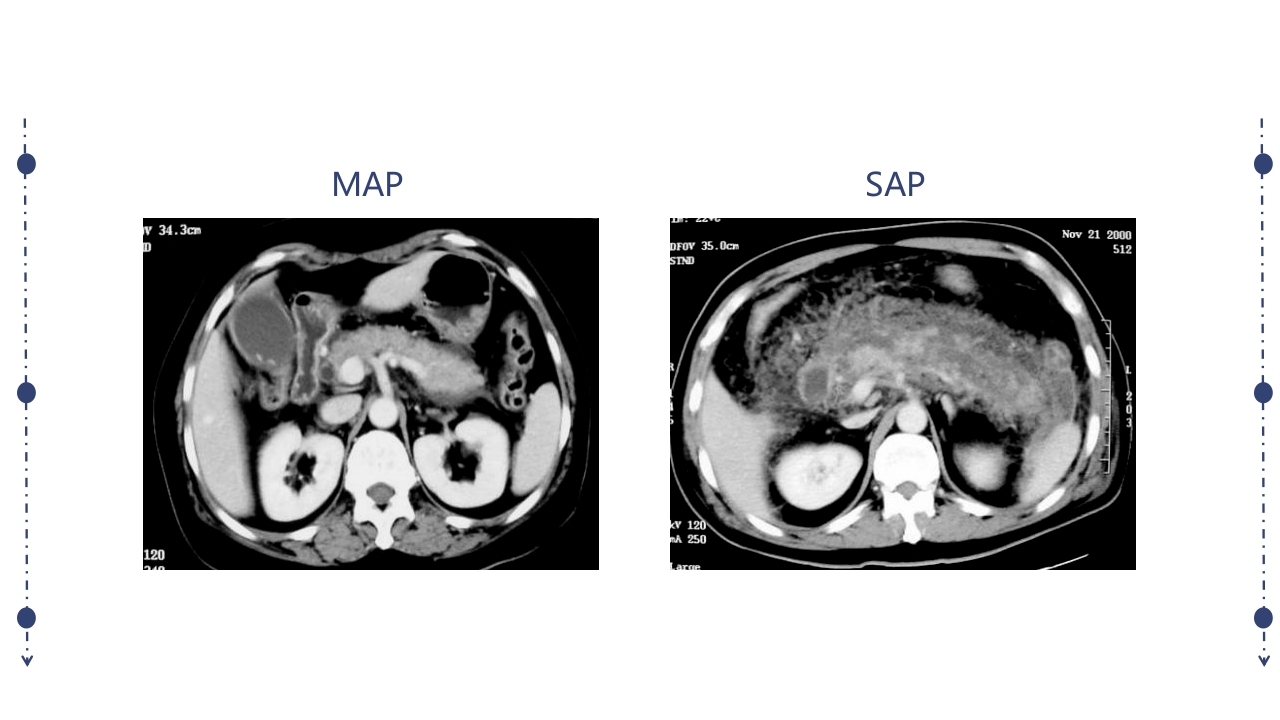

汇报人:xxx 病因 发病机制 病理变化 临床表现,实验室检查,辅助检查 严重程度评估 诊断及鉴别诊断 治疗 急性胰腺炎(AP)定义 急性胰腺炎(acute pancreatitis, AP)是多种病因导致胰酶激活,胰腺组 织自身消化所致的胰腺局部炎症反应(水肿、出血及坏死),病情较重可发 生全身炎症反应综合征(SIRS),并可伴有多脏器功能障碍的疾病。 临床表现以急性上腹痛、恶心、呕吐、发热、血 清胰酶增高等为特点。 常在饱食、脂餐、饮酒后发生。 胰腺的解剖位置 胰管、胆总管共同开口于十二 指肠大乳头肝胰壶腹部 共同通道学说(70-80%) 1. 胆道疾病 2. 酒精 3. 胰管阻塞 4. 十二指肠降部病变 5. 手术与创伤 6. 代谢障碍 7. 药物 8. 感染及全身炎症反应 9....